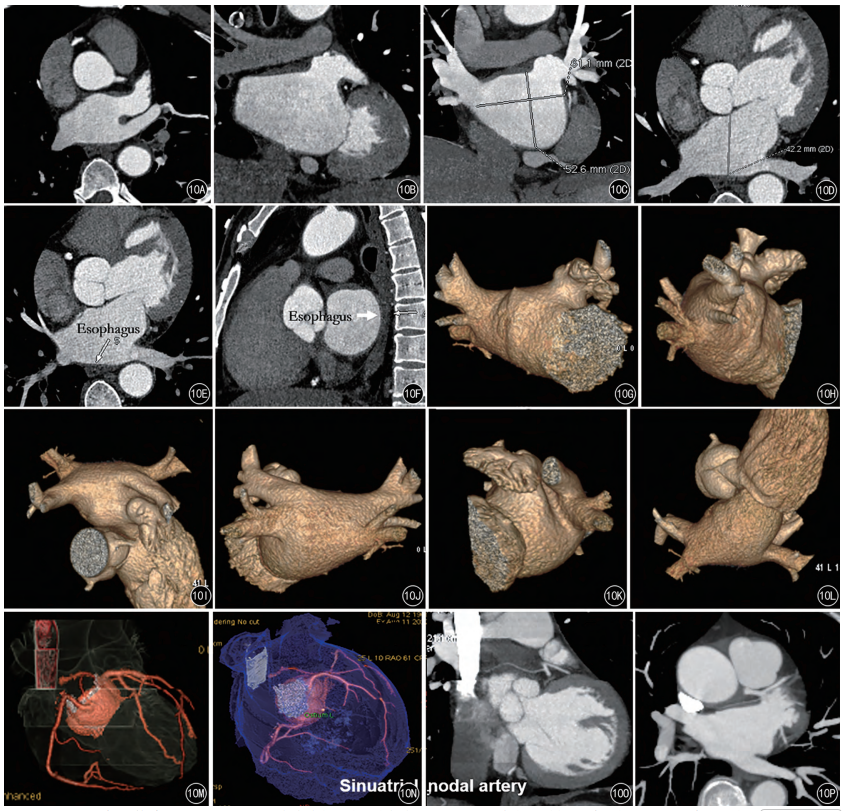

左心房-肺静脉CTA建议双期扫描,间隔60s,用于排除左心耳血栓,观察左心房、心耳、肺静脉形态结构,食管与心房的位置,指导房颤消融路径。三维重组需求见图1。

图1A~P 左心房-肺静脉CTA重组

注:A、B.最大密度投影(MIP)方式显示左心耳形态(对比剂充盈完整);C、D.左心房测量(上下、左右、前后直径);E、F.食管与左心房解剖关系(轴位+矢状位);G~L.容积再现(VR)三维重组显示肺静脉、左心房形态(PA、AP、RL、LL、Sup、Inf